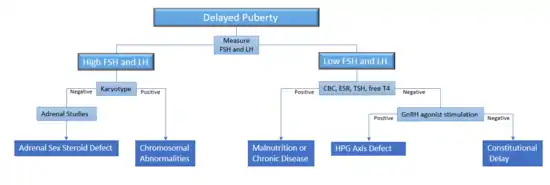

Lab tests

The first step in evaluating children with delayed puberty involves differentiating between the different causes of delayed puberty. Constitutional delay can be evaluated with a thorough history, physical, and bone age.[4] Malnutrition and chronic diseases can be diagnosed through history and disease-specific testing.[3] Screening studies include a complete blood count, an erythrocyte sedimentation rate, and thyroid studies[3]. Hypogonadism can be differentiated between hyper- and hypo-gonadotropic hypogonadism by measuring serum follicle-stimulating hormone (FSH) and luteinizing hormone (LH) (gonadotropins to measure pituitary output), and estradiol in girls (to measure gonadal output).[7][39] By the age of 10-12, children with failure of the ovaries or testes will have high LH and FSH because the brain is attempting to jump-start puberty, but the gonads are not responsive to these signals.[7][3]

Stimulating the body by administering an artificial version of gonadotropin-releasing hormone (GnRH, the hypothalamic hormone) can differentiate between constitutional delay of puberty and a GnRH deficiency in boys, although no studies have been done in girls to prove this.[7][42] It is often sufficient to simply measure the baseline gonadotrophin levels to differentiate between the two.[10]

In girls with hypogonadotropic hypogonadism, a serum prolactin level is measured to identify if they have the pituitary tumor prolactinoma. High levels of prolactin would warrant further testing with MRI imaging, except if drugs inducing the production of prolactin can be identified.[7] If the child has any neurological symptoms, it is highly recommended that the physician obtains a head MRI to detect possible brain lesions.[7]

In girls with hypergonadotropic hypogonadism, a karyotype can identify chromosomal abnormalities, the most common of which is Turner syndrome.[7] In boys, a karyotype is indicated if the child may have a congenital gonadal defect such as Klinefelter syndrome.[3] In children with a normal karyotype, defects in the synthesis of the adrenal steroid sex hormones can be identified by measuring 17-hydroxylase, an important enzyme involved in the production of sex hormones.[7]